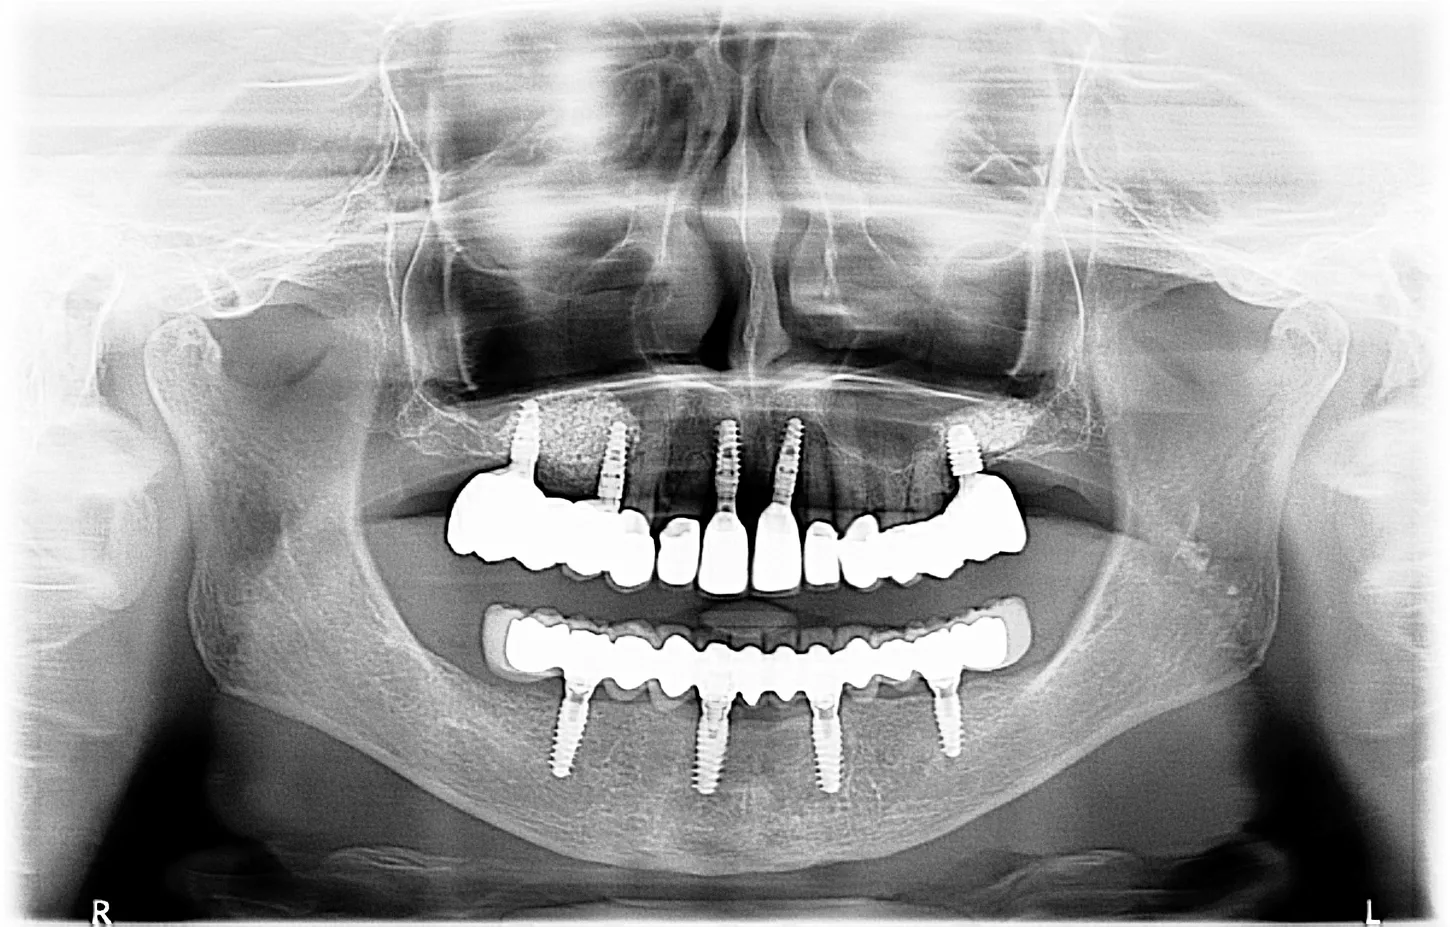

12.  The postoperative OPG shows the implant placement as planned

17.  Final control OPG with the complete treatment of the upper and lower jaw.